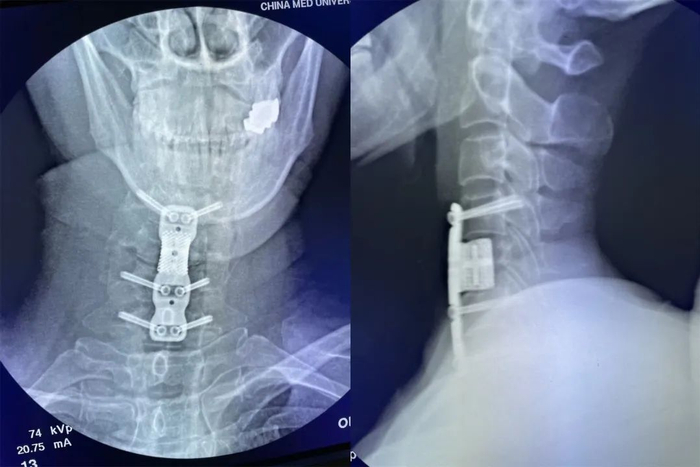

患者术前骨折影像

金属3D打印假体及颈椎前路椎弓根螺钉置入后影像